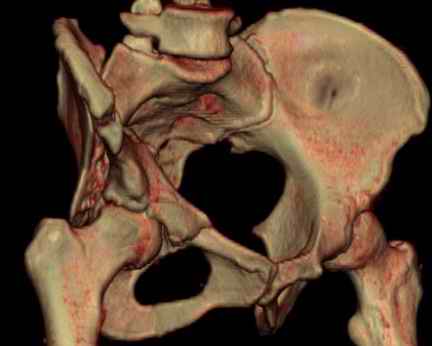

Посылаю схемы и 3D реконструкцию подобного повреждения. Называется он полным высоким двухколонным переломом вертлужной впадины, а "переломы крыла и тела подвздошной кости" входят в это понятие.

Вариантов остеосинтеза много (можно и не оперировть, т.к. конгруентность при таких переломах как правило сохраняется)

1 закрытая репозиция аппаратом + фиксация через проколы винтами

2 закрытая репозиция передней колонны + открытая задней колонны из задне-неружного доступа

3 открытая репозиция передней колонны из подвздошнго доступа + открытая задней колонны из задне-наружного доступа

4 открытая репозиция из илиоингвинального доступа

5 открытая репозиция из Y образного доступа

Я бы ориентировался на Y образный доступ

или из двух если есть сомнения в целостности задних отделов крыла.

прикладываю схему доступа и случай.

Одним задне наружным переднюю колонну не достать, а илио-ингвинальный более сложный не позволяет контролировать суставную поверхность и трудно управлять задней колонной.